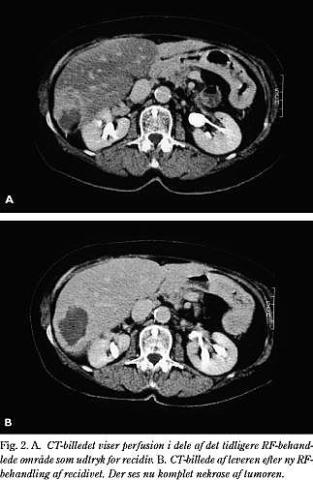

Hvis CT-billedet viste et uregelmæssigt afgrænset behandlingsområde med perfusion i dele af det behandlede område eller delvis kontrastopfyldning af RF-ablationen i den forsinkede fase, blev det vurderet som inkomplet nekrose (Fig. 2 ).

Såfremt der fandtes rest af tumorvæv i det koagulerede område, eller der ved kontroller fandtes nytilkomne metastaser (antal 4), blev der foretaget en ny RF-ablation.